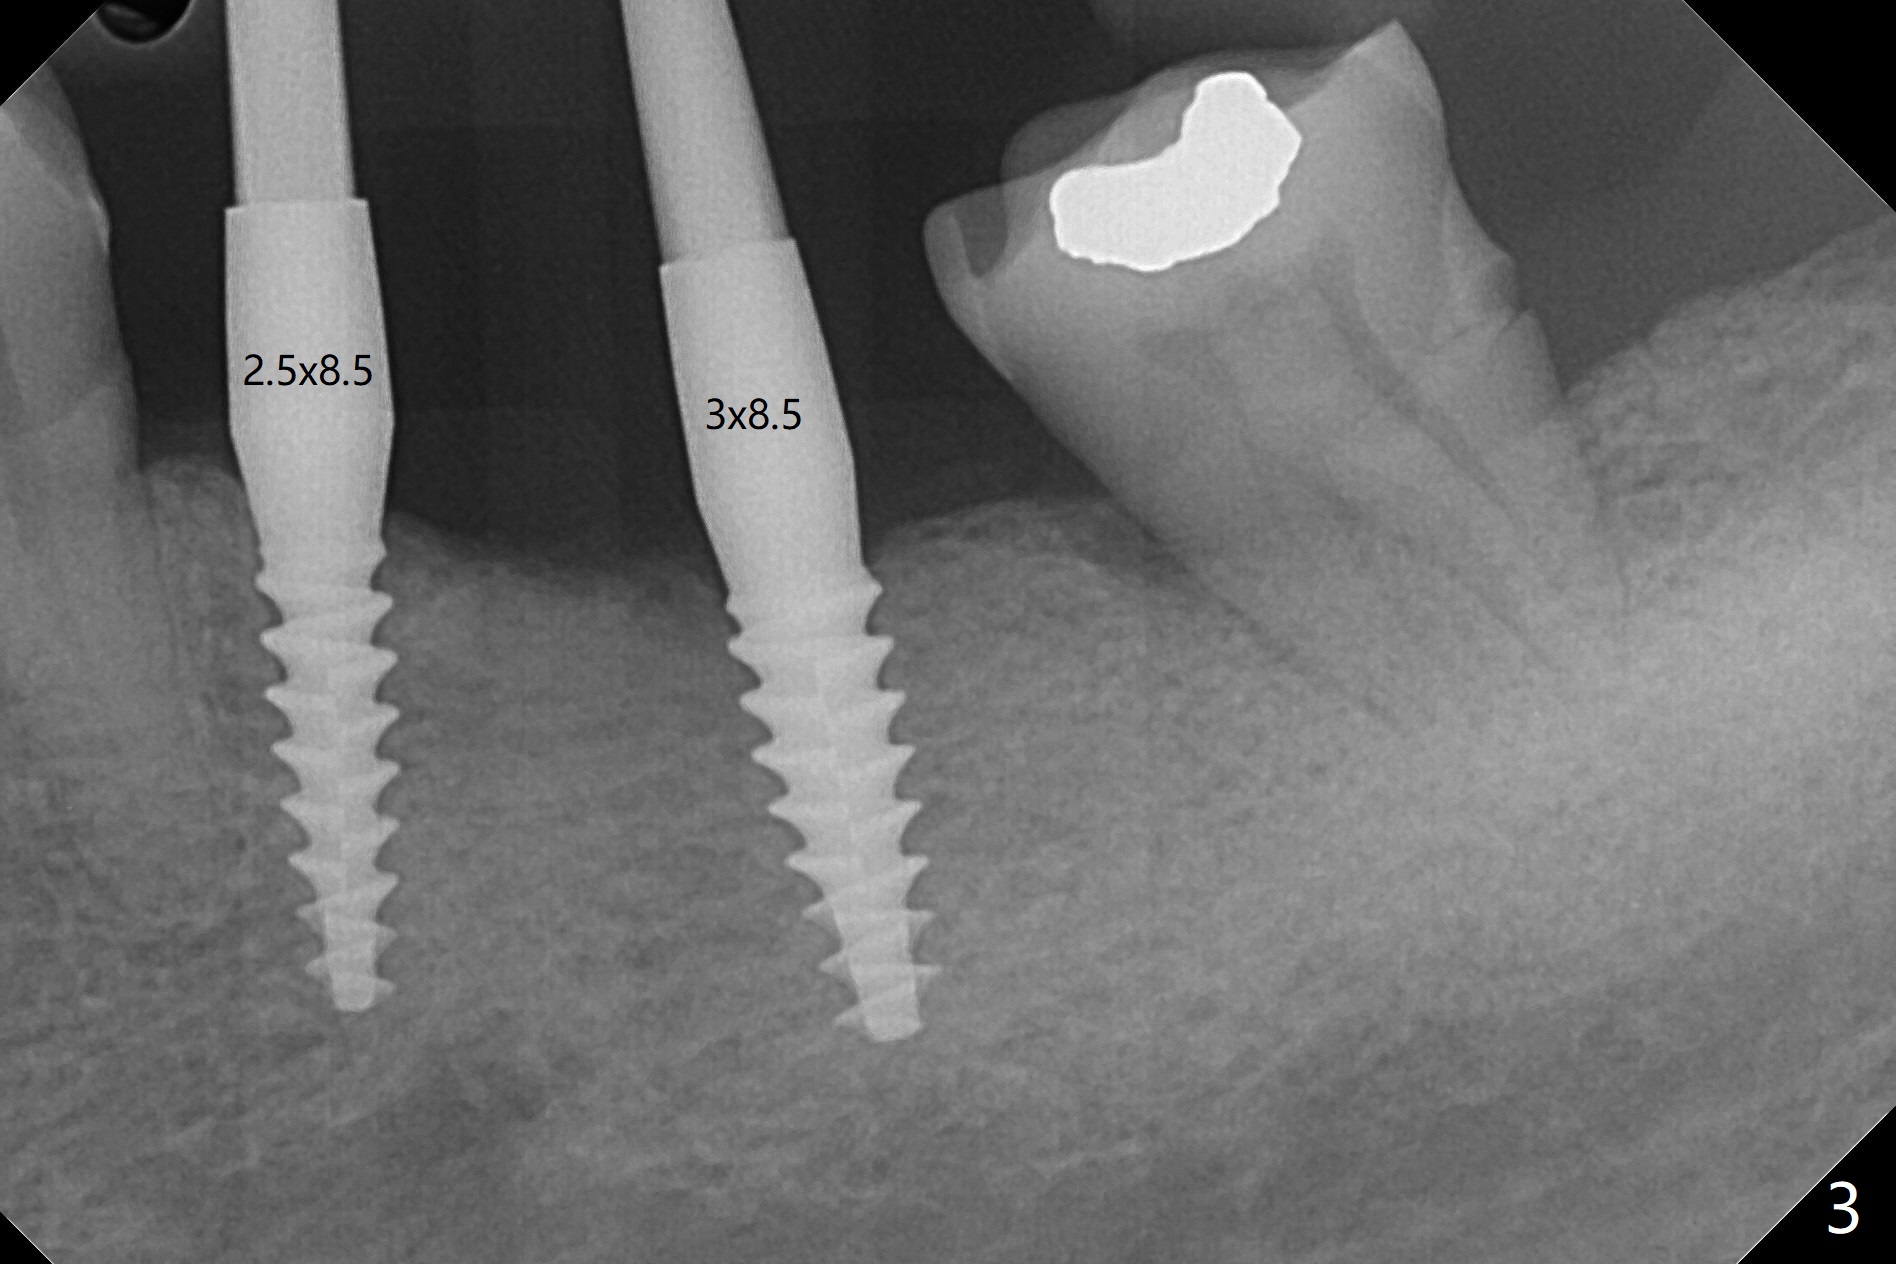

左下5,6切开,使用导板钻洞,都偏向颊侧(图一),好像牙槽嵴太狭窄,不适合做劈开术,然后改为自由手,使用Lindermann(侧方)钻头将钻洞往舌侧迁移,完成一段式植体初步钻洞(图二)以及植体植入(图三:2.5毫米(直径),根据近远中距离,植体不显得太窄)。尽管下齿槽神经阻断麻醉(开始浸润麻醉),病人疼痛明显,不敢下沉远中植体太多(图四:>),放置粘性骨块(图五,六:*)和PRF膜。缝合后,调整基台以及对合牙高度(图六: <),最后放置牙周敷料。由于植骨,术后15天植体周围形成致密的牙龈带(图七:*(gingival band))。术后一个月安置临时连体牙冠,没有任何咬合接触,主要目的防止7近中倾斜。术后三个半月临时牙冠被吞入,右侧托牙也不见了,局部牙龈健康,塞入2-0 gingival retraction cord(增加5基台长度(今后牙冠固位),图八 (>:植体螺丝刀终止地方)),取模。永久性牙冠边缘不重要,由实验室决定。清除残余粘固剂也不是很困难(图九)。